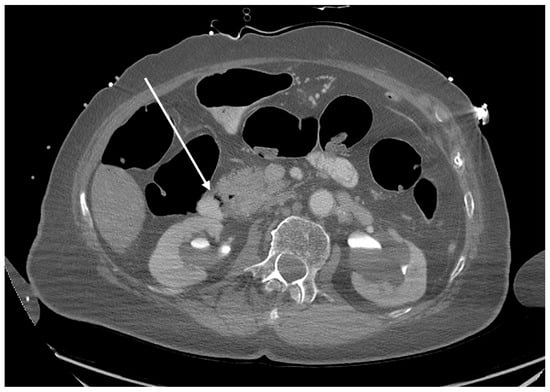

Figure 1. Axial plane of the abdominopelvic CT scan after intravenous contrast administration (lung window) at the level of the liver. Extensive intrahepatic gas is visible within the bile ducts (arrow).

The pathway of CO2 gas transmission also occurs by the biliary tract; the gas then enters the vessels of the circulatory system through the injured endothelium. The pathomechanism and incidence of this complication are multifactorial. The type of endoscopes used and the working pressure of the gas used, the type of intervention, the presence of biliary-venous fistulas, the state of the mucosal barrier, previous endoscopic interventions or the presence of implanted foreign materials are all significant [3]. All these factors result in a breach of the endothelial and tissue barrier with the transmission of gas into the vascular system—the portal vein runoff or the hepatic venous system. Figure 1 shows bile ducts filled with gas. The transmission of CO2 into the superior vena cava system occurred via damage to the endothelial tissue barrier between the bile ducts and the hepatic veins.